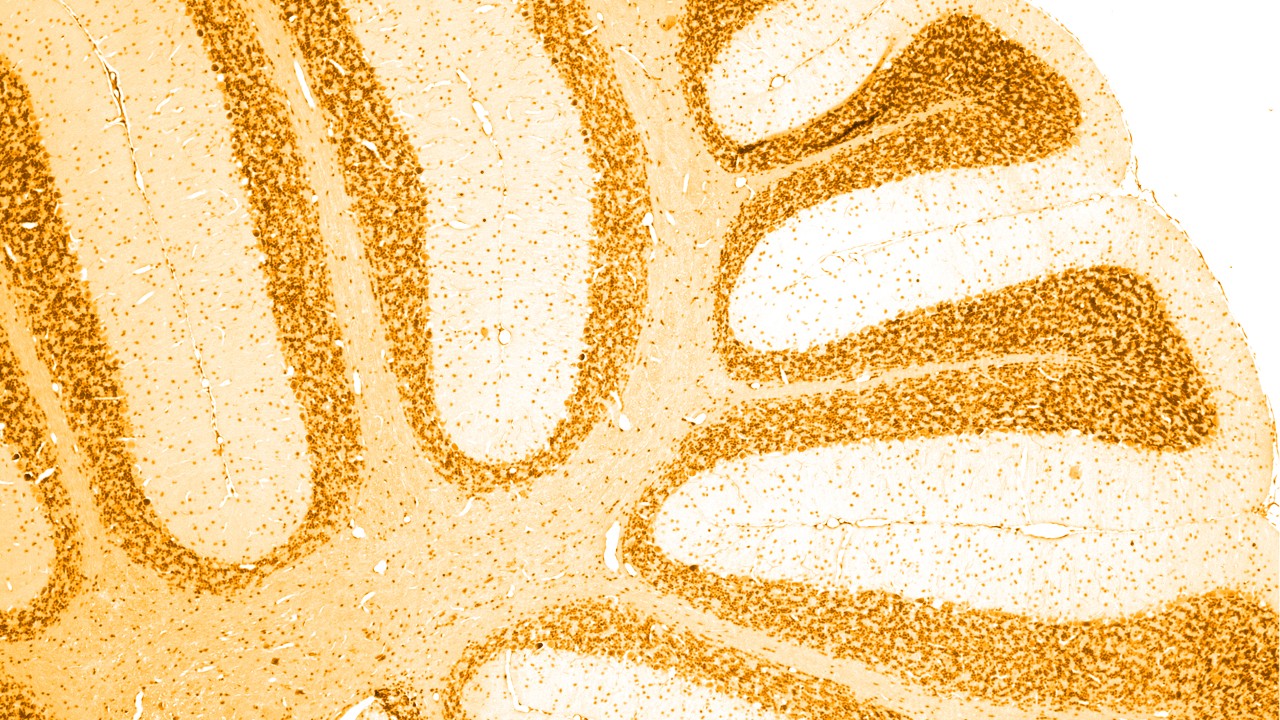

Comprendre les maladies neurologiques

Les maladies neurologiques affectent le système nerveux central et périphérique et donc le cerveau, la moelle épinière et tous les nerfs et muscles qui régulent et coordonnent les fonctions corporelles.